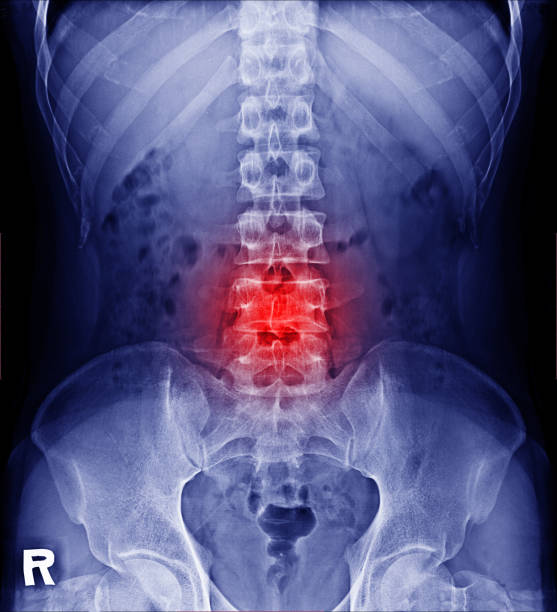

허리디스크 4번 5번 증상 정리

지난 포스팅에서 허리디스크의 전반적인 증상에 대해 설명해 드렸으니, 이번에는 가장 흔하게 발생하는 허리디스크 4번 5번의 주요 원인과 증상을 더욱 상세히 나누어 알아보겠습니다.

우리 척추 중에서 요추 4번과 5번은 일상생활 시 하중을 가장 크게 견뎌야 하는 부위라서 디스크 탈출증이 아주 쉽게 발생합니다. 구부정한 자세로 장시간 앉아 있거나 무거운 물건을 무리하게 들어 올릴 때 척추뼈 사이의 압력이 급격하게 증가하게 됩니다. 저 역시 항상 구부정하게 스마트폰과 태블릿을 보고 허리를 한쪽 방향으로만 회전하는 운동을 즐기다 보니 허리를 자꾸 삐끗하곤 했습니다.